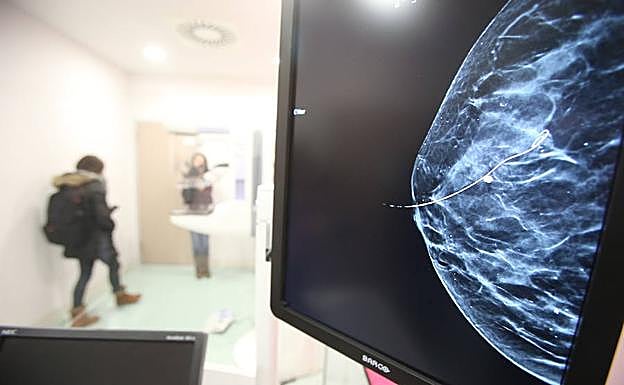

Imagen de una mMamografía.

Un alto porcentaje de pacientes de cáncer de mama y pulmón podrían evitar la quimioterapia e incluso tener una mayor esperanza de vida, según dos estudios difundidos este domingo en la reunión anual de la Sociedad Estadounidense de Oncología Clínica, en Chicago, EE UU.

El primer estudio, descrito como la prueba de cáncer de mama más inclusiva hasta la fecha, encontró que la mayoría de las mujeres con un tipo común de cáncer de mama podría evitar la quimioterapia después de la cirugía, dependiendo de su puntaje en una prueba genética.